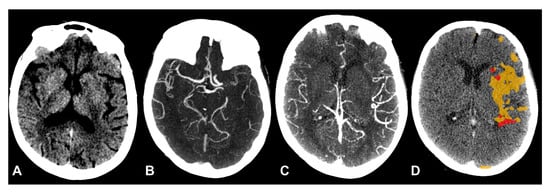

Collateral Status Evaluation Using CT Angiography and Perfusion Source Images in Acute Stroke Patients

by

Heitor C. B. R. Alves, Bruna G. Dutra, Vivian Gagliardi, Rubens J. Gagliardi, Felipe T. Pacheco, Antonio C. M. Maia, Jr. and Antônio J. da Rocha

Brain Sci. 2025, 15(10), 1092; https://doi.org/10.3390/brainsci15101092 - 9 Oct 2025

Background/Objectives: Single-phase CT angiography (sCTA) is widely used to assess collateral circulation in acute ischemic stroke, but its static nature can lead to an underestimation of collateral flow. Our study aimed to develop and validate a direct, qualitative dynamic CTA (dCTA) collateral score

Background/Objectives: Single-phase CT angiography (sCTA) is widely used to assess collateral circulation in acute ischemic stroke, but its static nature can lead to an underestimation of collateral flow. Our study aimed to develop and validate a direct, qualitative dynamic CTA (dCTA) collateral score based on CTP source images, without the need for post-processing software, to provide a more accurate prognostic tool. Methods: We retrospectively analyzed 112 patients with anterior circulation ischemic stroke from a prospective registry who underwent non-contrast CT, sCTA, and CTP within 8 h of onset. Collateral circulation was graded using a 4-point sCTA score and our novel 4-point dCTA score, which incorporates temporal filling patterns. We used linear regression to compare the association of both scores with CTP-derived core/hypoperfusion volumes, infarct growth, and final infarct volume. Results: The dCTA method frequently reclassified patients with poor collaterals on sCTA to good collaterals on dCTA (n = 23), while the reverse was rare (n = 5). A better collateral score was significantly associated with smaller core volume for both sCTA and dCTA, but the dCTA score demonstrated a superior model fit (R2 = 0.36 vs. 0.32). Similar superior correlations for dCTA were observed for hypoperfusion, infarct growth, and final infarct volumes. Critically, only the dCTA score significantly modified the association between core volume and time since stroke onset (p for interaction = 0.04). Conclusions: A collateral score derived from CTP source images (dCTA) offers a more reliable prediction of infarct lesion sizes and progression than conventional sCTA. By incorporating temporal resolution without requiring extra software, dCTA provides a robust correlation with stroke temporal evolution and represents a readily implementable tool to enhance patient selection in acute stroke.